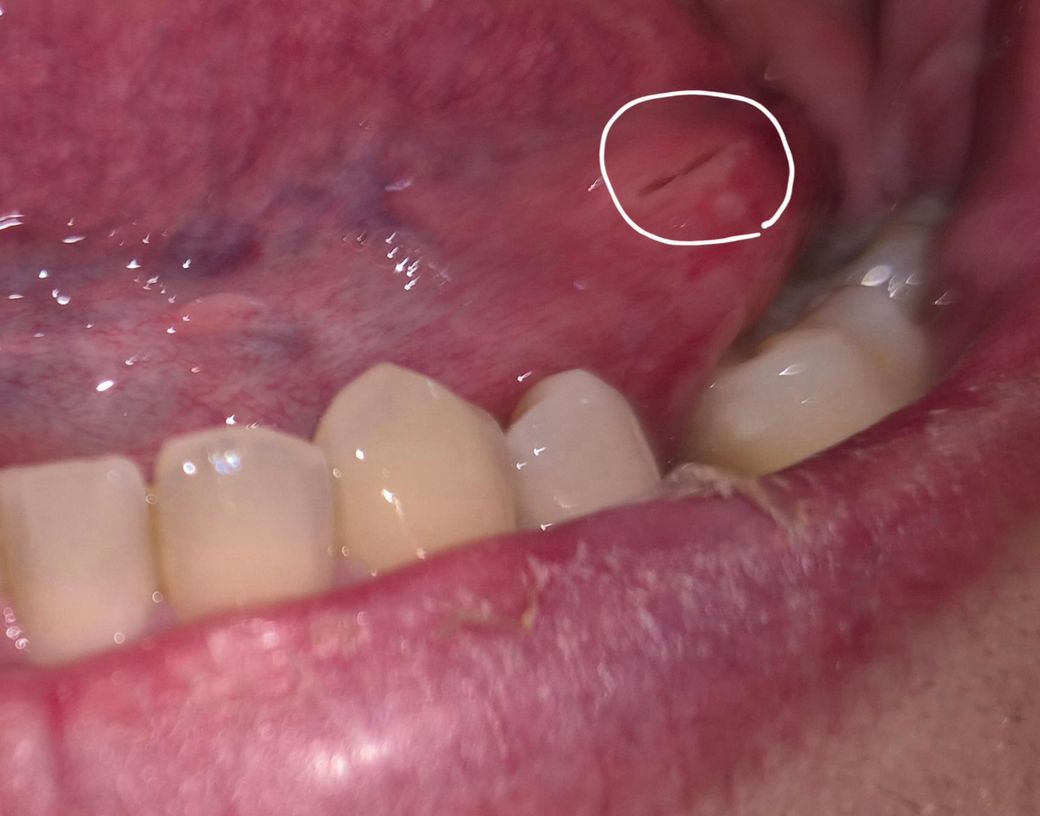

혀를 씹어서 상처가 났어요 어떻게 해야 하나요?

피는 금방 멈췄으나 상처가 갈라져 있는 상태입니다. 크게 통증이나 부어오름은 없어요. 며칠간 오라메디 바르면서 냅두면 될까요?

• 1번 째 사진